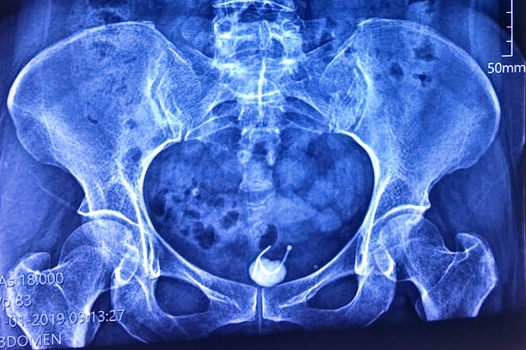

Ảnh chụp X-quang cho thấy vòng tránh thai bị mắc kẹt ở bàng quang người phụ nữ. Ảnh: BSCC

Bệnh nhân là bà T.T.H, 54 tuổi, ngụ Đồng Nai nhập viện trong tình trạng đau bụng vùng hạ vị kèm tiểu khó. Qua thăm khám kết hợp với kết quả siêu âm, bác sĩ phát hiện bệnh nhân có dị vật hình chữ T qua thành bàng quang và có sỏi bàng quang.

Bác sĩ Phan Văn Ở, Phó Giám đốc bệnh viện cho biết, dị vật là chiếc vòng tránh thai hình chữ T. Chiếc vòng này theo như bệnh nhân kể thì đã được đặt từ 31 năm trước, song đã bị rơi khỏi vị trí cố định ban đầu, chiếc vòng đi xuyên thành bàng quang và tạo sỏi đã làm chị H. đau bụng và tiểu khó.

- Bệnh nhân nữ đau bụng ở hạn vị kèm theo tiểu khó, qua thăm khám chụp X-quang bác sĩ phát hiện thủ phạm là chiếc vòng tránh thai cũ xuyên qua bàng quang.